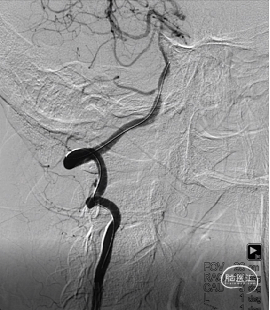

2021-09-24DSA

右侧椎动脉开口重度狭窄,右侧颈动脉C6段中度狭窄

RVA

右椎动脉开口重度狭窄,V4段发出小脑后下动脉处局部重度狭窄底动脉

LVA

左侧椎动脉开口闭塞,锁骨下动脉未见椎动脉残端,V2段由甲颈干及肋颈干代偿,并汇入基底动脉

重要操作简述:右椎开口重度狭窄

重要操作简述:指引管造影确认V4段狭窄

影像结论:右椎V4段残余狭窄约20%

影像结论:右椎开口残余20%